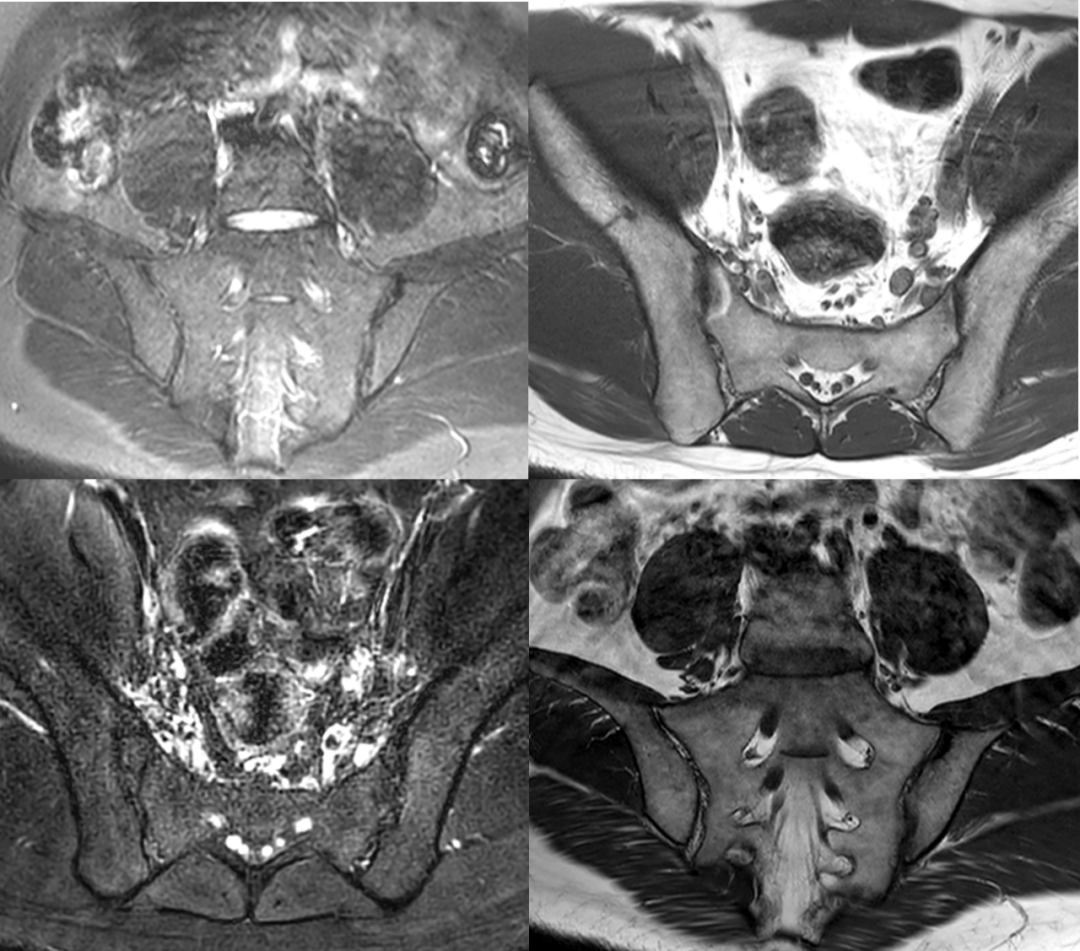

- 影像學檢查,如X光或核磁共振成像